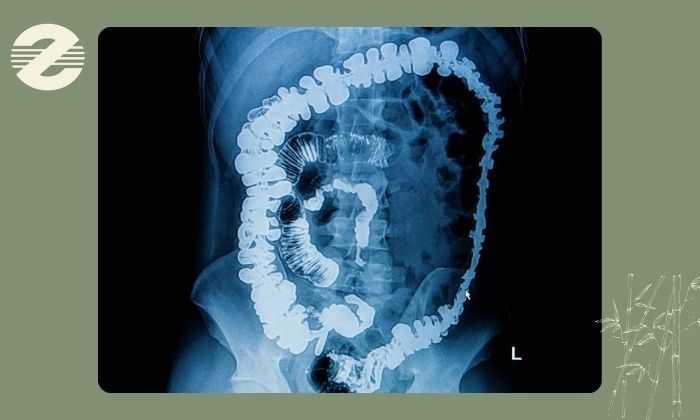

باریم انما و کولونوسکوپی در بررسی روده بزرگ